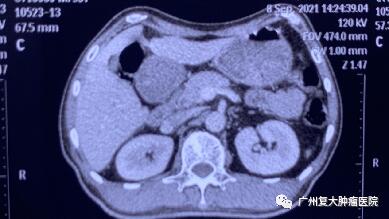

術(shù)后一周檢查發(fā)現(xiàn),身體各項(xiàng)指標(biāo)逐步恢復(fù)正常。與之前相比,上腹部MRI圖像提示胰腺、肝臟腫瘤中心大部分壞死。術(shù)后一年復(fù)查顯示,腫瘤縮小,得到較好的控制。

▲術(shù)后一周

▲術(shù)后一年